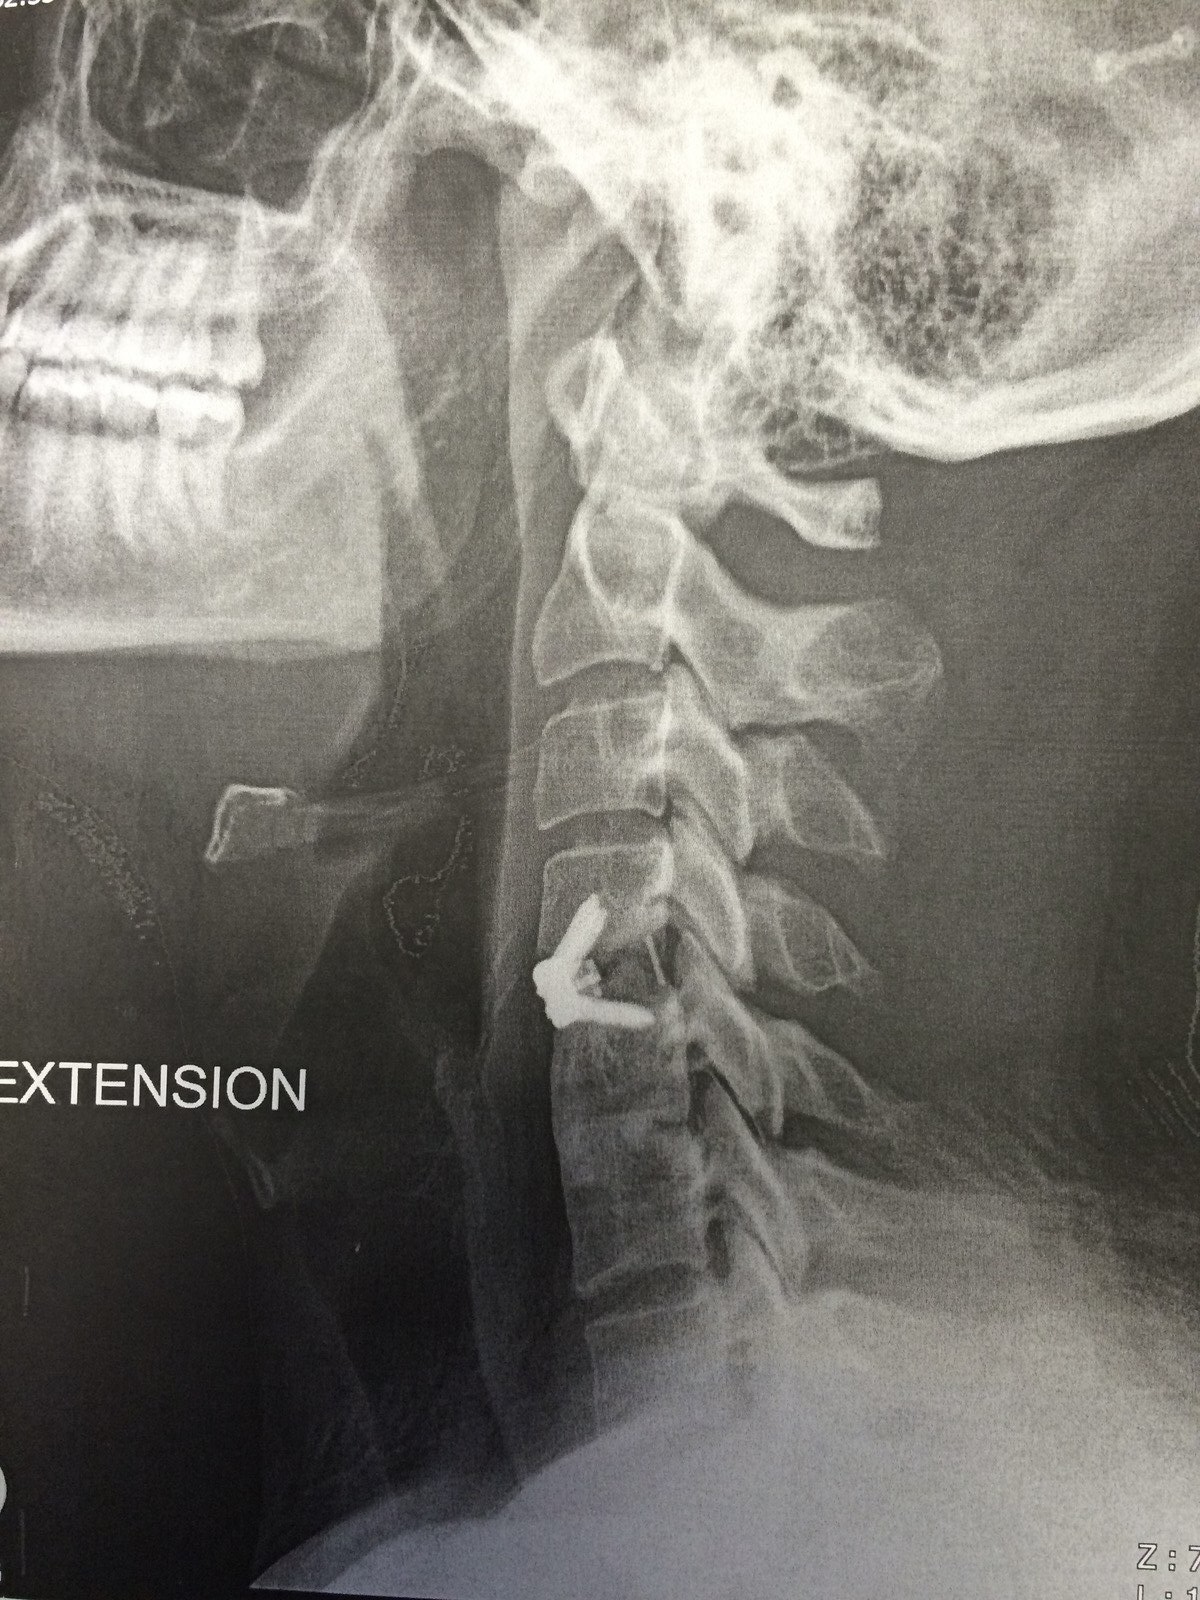

의료 팀은 영상 진단을 통해 얻은 정보를 바탕으로 수술 계획을 세웁니다. 손상된 디스크의 위치, 척추의 구조적 문제, 신경 압박의 정도 등을 고려하여 수술 접근 방법과 필요한 기구를 결정합니다.

수술은 주로 목의 앞쪽(전방 접근법) 또는 뒤쪽(후방 접근법)을 통해 이루어집니다.

전방 접근법은 대부분의 경우에 사용되며, 손상된 디스크와 신경에 보다 쉽게 접근할 수 있게 해줍니다.